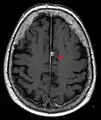

![]() Cross-sectional T1-weighted MRI of a healthy human brain acquired with an ultra high-field MR of 7 Tesla field strength | |

- T1 (note CSF is dark) with contrast (arrow pointing to meningioma of the falx)